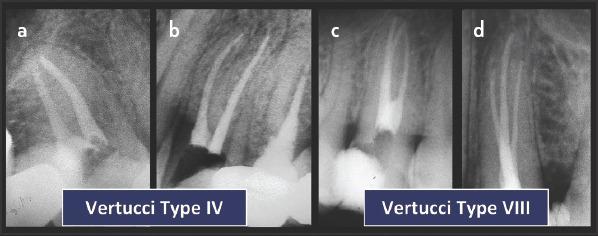

应用根管解剖分类新系统于临床实践:说明与详述。

Application of a new System for Classifying Root and Canal Anatomy in Clinical Practice - Explanation and Elaboration.

Adequate understanding and accurate characterization of normal and unusual root and canal morphology are essential requirements for successful root canal treatment. A new coding system for classifying root and canal morphology, accessory canals and anomalies has been introduced. In addition to technological advances related to experimental studies involving micro-computed tomography, the continuing clinical advances in magnification, illumination, imaging and intra-operative root canal treatment procedures have allowed clinicians to identify an increasingly wide range of anatomical variations in roots and canals in an attempt to achieve more predictable clinical outcomes. This review aims to provide a step-by-step explanation for the clinical application of the new coding system in dental practice, and to describe the anatomical variations in roots and canals for teeth scheduled for root canal treatment.

充分理解和准确描述正常和异常的牙根和根管形态是根管治疗成功的基本要求。引入了一种新的根管形态、副根管和异常分类编码系统。除了与涉及微计算机断层扫描的实验研究相关的技术进步外,放大、照明、成像和术中根管治疗程序的持续临床进展使临床医生能够识别越来越广泛的根和根管的解剖变异,试图实现更可预测的临床结果。本综述旨在为新编码系统在牙科实践中的临床应用提供逐步解释,并描述计划进行根管治疗的牙齿的牙根和根管的解剖变异。